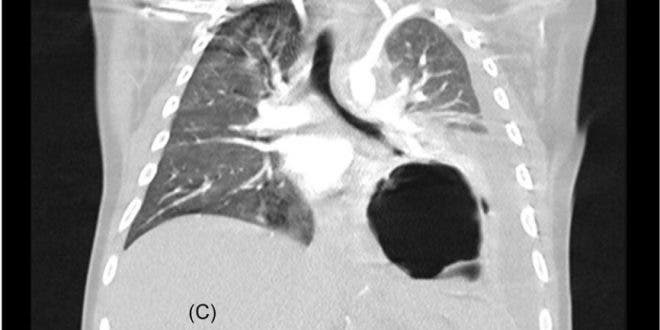

• Inflamación de órganos como corazón, pulmones, riñones, cerebro, piel ojos u órganos gastrointestinales